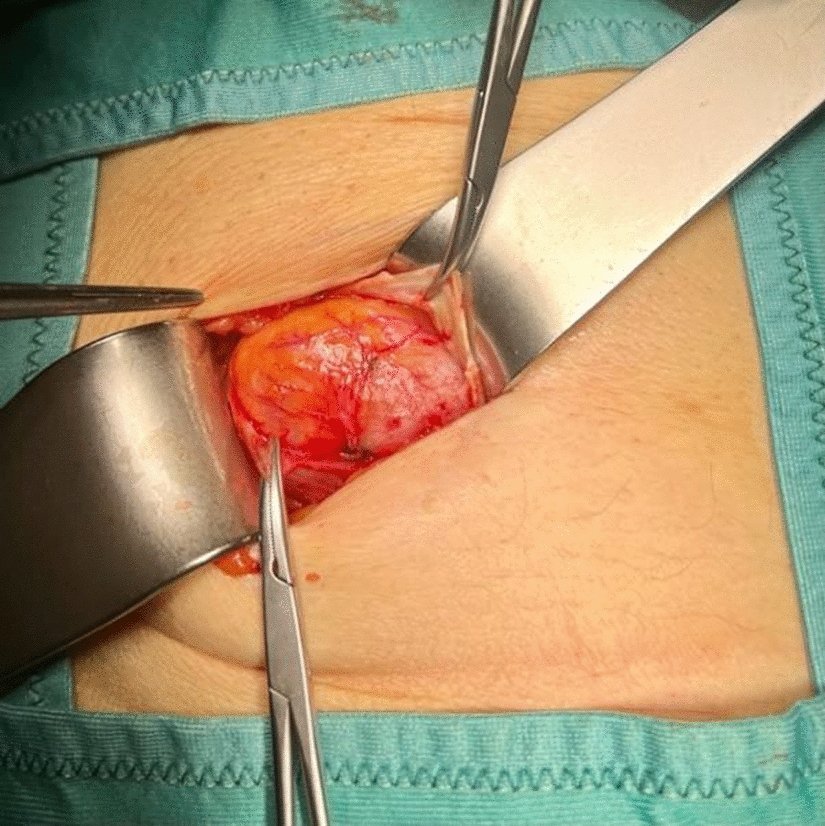

• Figs. 6, 7, 8, 9, 10: intraoperative findings and repair steps with mesh insertion in selected cases

Fig. 7

Selected intraoperative picture with spigelian hernia sac (Foto

© R. Lorenz)

Bild vergrößern

Fig. 8